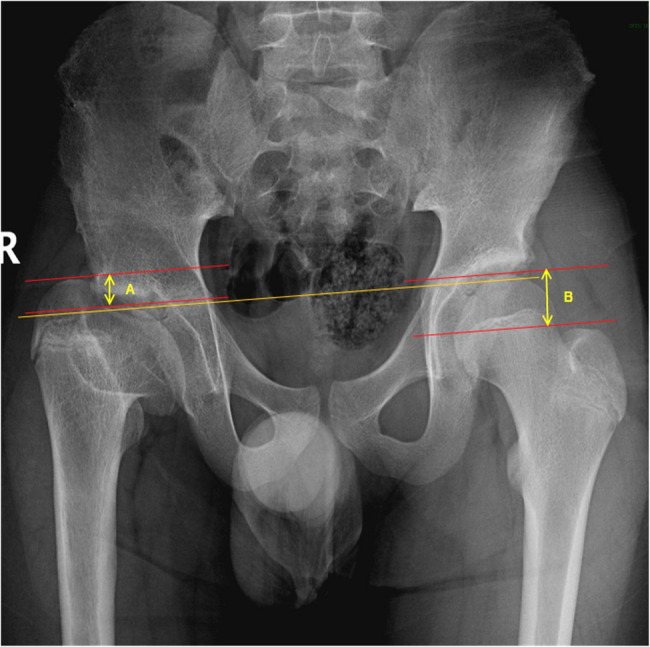

Risk factors associated with greater trochanteric overgrowth secondary to Legg-Calvé-Perthes disease: a retrospective observational study.